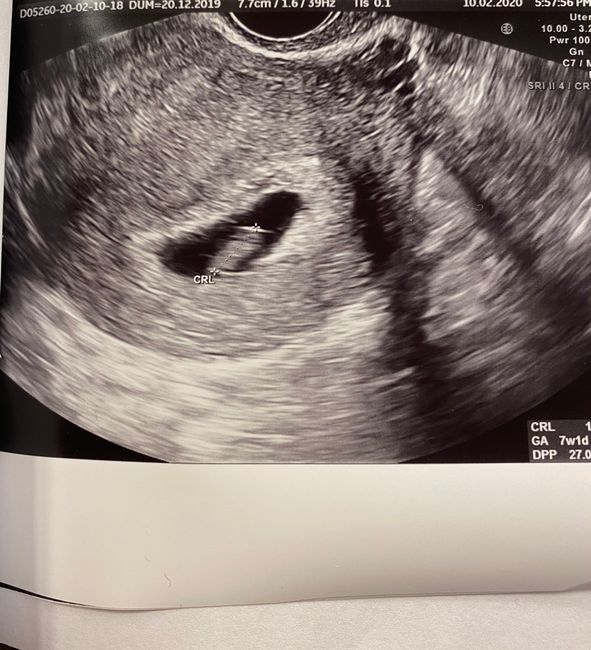

2186 giorni fa

Ciao ragazze qualche gg fa ho scoperto di aspettare un maschietto anche se mi avevano detto prima che era femminuccia infatti sono rimasta abbastanza scioccata mente mi faceva l'ecografia.. mi ero fissata troppo mi sa! Vi allego le mie eco.. è sicuro...